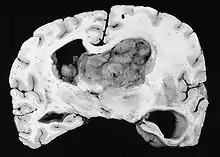

Subependymal giant cell astrocytoma

Subependymal giant cell astrocytoma (SEGA, SGCA, or SGCT) is a low-grade astrocytic brain tumor (astrocytoma) that arises within the ventricles of the brain.[1] It is most commonly associated with tuberous sclerosis complex (TSC). Although it is a low-grade tumor, its location can potentially obstruct the ventricles and lead to hydrocephalus.

| GFAP stained microscopic section of a subependymal giant cell astrocytoma | |